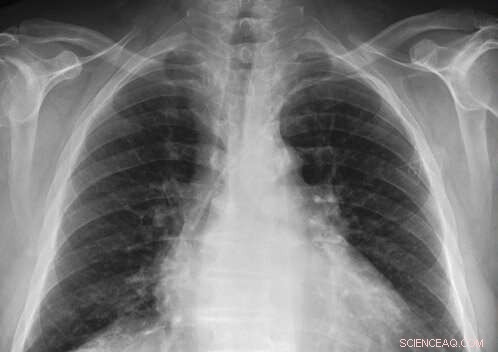

Researchers have released a repository of more than 350,000 detailed chest X-rays, which is free and open to academic, clinical, and industrial investigators. Credit: Massachusetts Institute of Technology

Last week, the MIT Laboratory for Computational Physiology, a part of the Institute for Medical Engineering and Science (IMES) led by Professor Roger Mark, launched a preview of their MIMIC-Chest X-Ray Database (MIMIC-CXR), a repository of more than 350,000 detailed chest X-rays gathered over five years from the Beth Israel Deaconess Medical Center in Boston. The project, like the lab's previous MIMIC-III, which houses critical care patient data from over 40,000 intensive care unit stays, is free and open to academic, clinical, and industrial investigators via the research resource PhysioNet. It represents the largest selection of publicly available chest radiographs to date.

With access to the MIMIC-CXR, funded by Philips Research, registered users and their cohorts can more easily develop algorithms for fourteen of the most common findings from a chest X-ray, including pneumonia, cardiomegaly (enlarged heart), edema (excess fluid), and a punctured lung. By way of linking visual markers to specific diagnoses, machines can readily help clinicians draw more accurate conclusions faster and thus, handle more cases in a shorter amount of time. These algorithms could prove especially beneficial for doctors working in underfunded and understaffed hospitals.